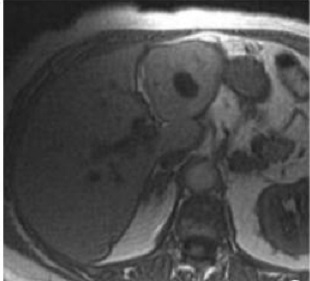

Image

radiologique IRM de kyste du foie : Image lesionel arrondie

ou ovalaire hyposignal en T1 et hypersignal en T2 et nette sủr

T1 + gadolinium FS

Image ỈRM ponderation T1

en coupe axiale d'une kyste simple du foie gauche ,avec

aspect lesionaire ovalaire a hyposignal situe au foie gauche

|

Meme cas

en ponderation T2 : Image lesionnel est tres hypersignal

situe au foie gauche |

Aspect de ce cas ponderee en

T1 + gadolium FS : Image ovalaire a hypodense du foie

gauche |